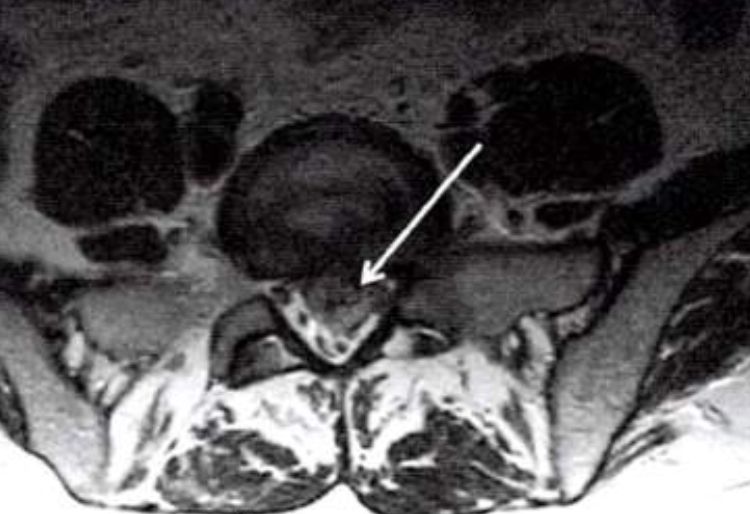

✔ 척추 협착증 → 신경이 지나가는 길(척추관)이 좁아지면서 신경을 압박하는 질환

✔ 디스크(추간판 탈출증) → 디스크가 돌출되면서 신경을 눌러 통증을 유발하는 질환

🚪 척추 협착증 → 신경이 지나가는 ‘통로’가 좁아진 경우

📦 디스크 → 디스크가 튀어나와 신경을 누르는 경우